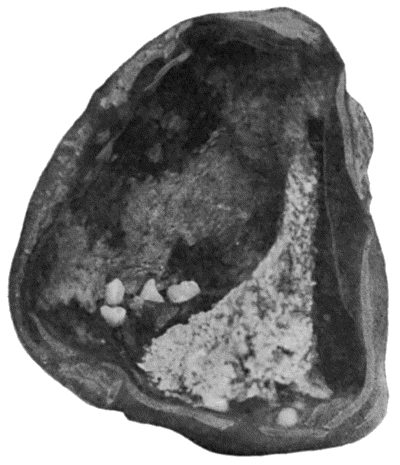

168.Multiple partially ossified Chondromas of Synovial Membrane from Shoulder-joint 542